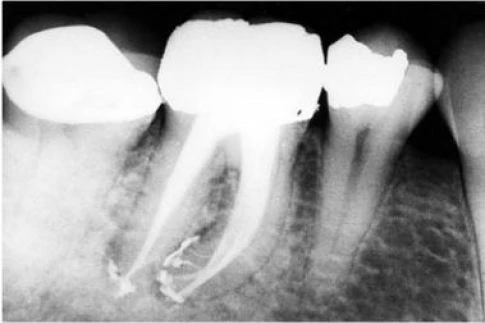

Mở xoang tủy nhìn chung răng cối lớn một hàm dưới có 2 chân phân biệt hình tròn hay thường là elip, ống tủy ở chân xa (hình 11.106) và 2 ống tủy ở chân răng gần. Trong 90% trường hợp chúng đổ ra 2 lỗ chóp khác nhau (hình 11.107) và 10% chúng hợp lại và đổ ra 1 lỗ chóp (hình 11.108).

Hình 11.106. Xoang tủy ở 1 R36: miệng củanhững ống tủy gần khá tròn còn ở ống tủy xa thì thường có hình elip.